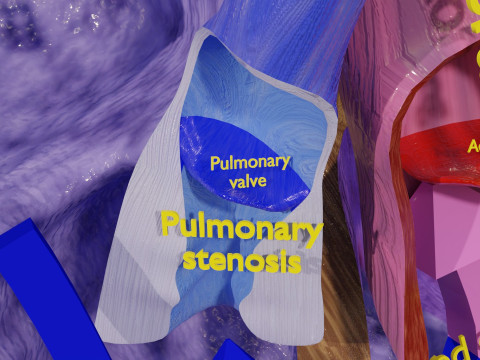

The model meshes include adult circulation versus circulation in Tetralogy of Fallot (TAF), arrow labels and text labels. The blood flow in a patient with Tetralogy of Fallot is outlined in this model. To contrast it to normal blood circulation a separate model of normal circulation is included. The Tetralogy of Fallot (OVER RIDING OF AORTA, PUL STENOSIS, VENTRICULAR SEPTAL DEFECT, RIGHT VENTRICULAR HYPERTROPHY), fossa, ligament teres , venosus, and arteriosus are duly depicted with proper labelling and blood flow directional arrows. Excellent model for teaching, demonstration and knowlegde of human body. The models include both procedural and image textures blend files separately. The texture file include diffuse, roughness and normal png and jpeg based on non overlapping UV maps.